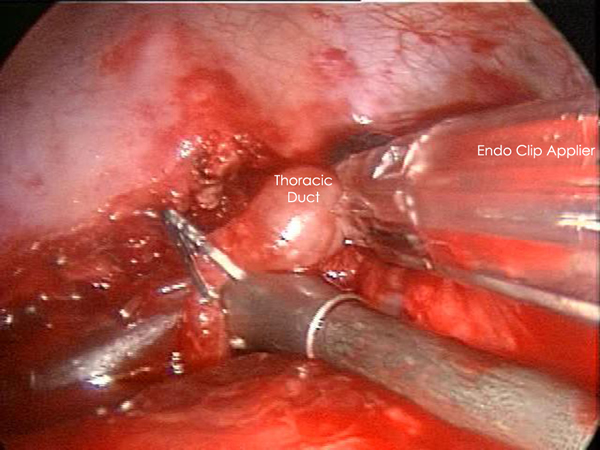

Exploration of this area bluntly will reveal the thoracic duct as a thin tubular structure with occasional peristalsis (Video 5). Once a sufficient length of duct is isolated it is doubly clipped using 5 or 10mm clips depending on the size of the duct and is divided (Figures 4-6). Transection with a linear cutting stapler with a vascular load (30mm length, 2.0mm staple height) works just as well (Video 6). The stapler or clip applier can be introduced through the working incision or the incision used for retraction of the diaphragm. If an adequate length of the duct can be isolated, a portion can be excised and sent for frozen section to confirm its identity.

| Figure 4: Thoracic Duct isolation. | Figure 5: Thoracic Duct Ligation. | Figure 6: Thoracic Duct Divided. |